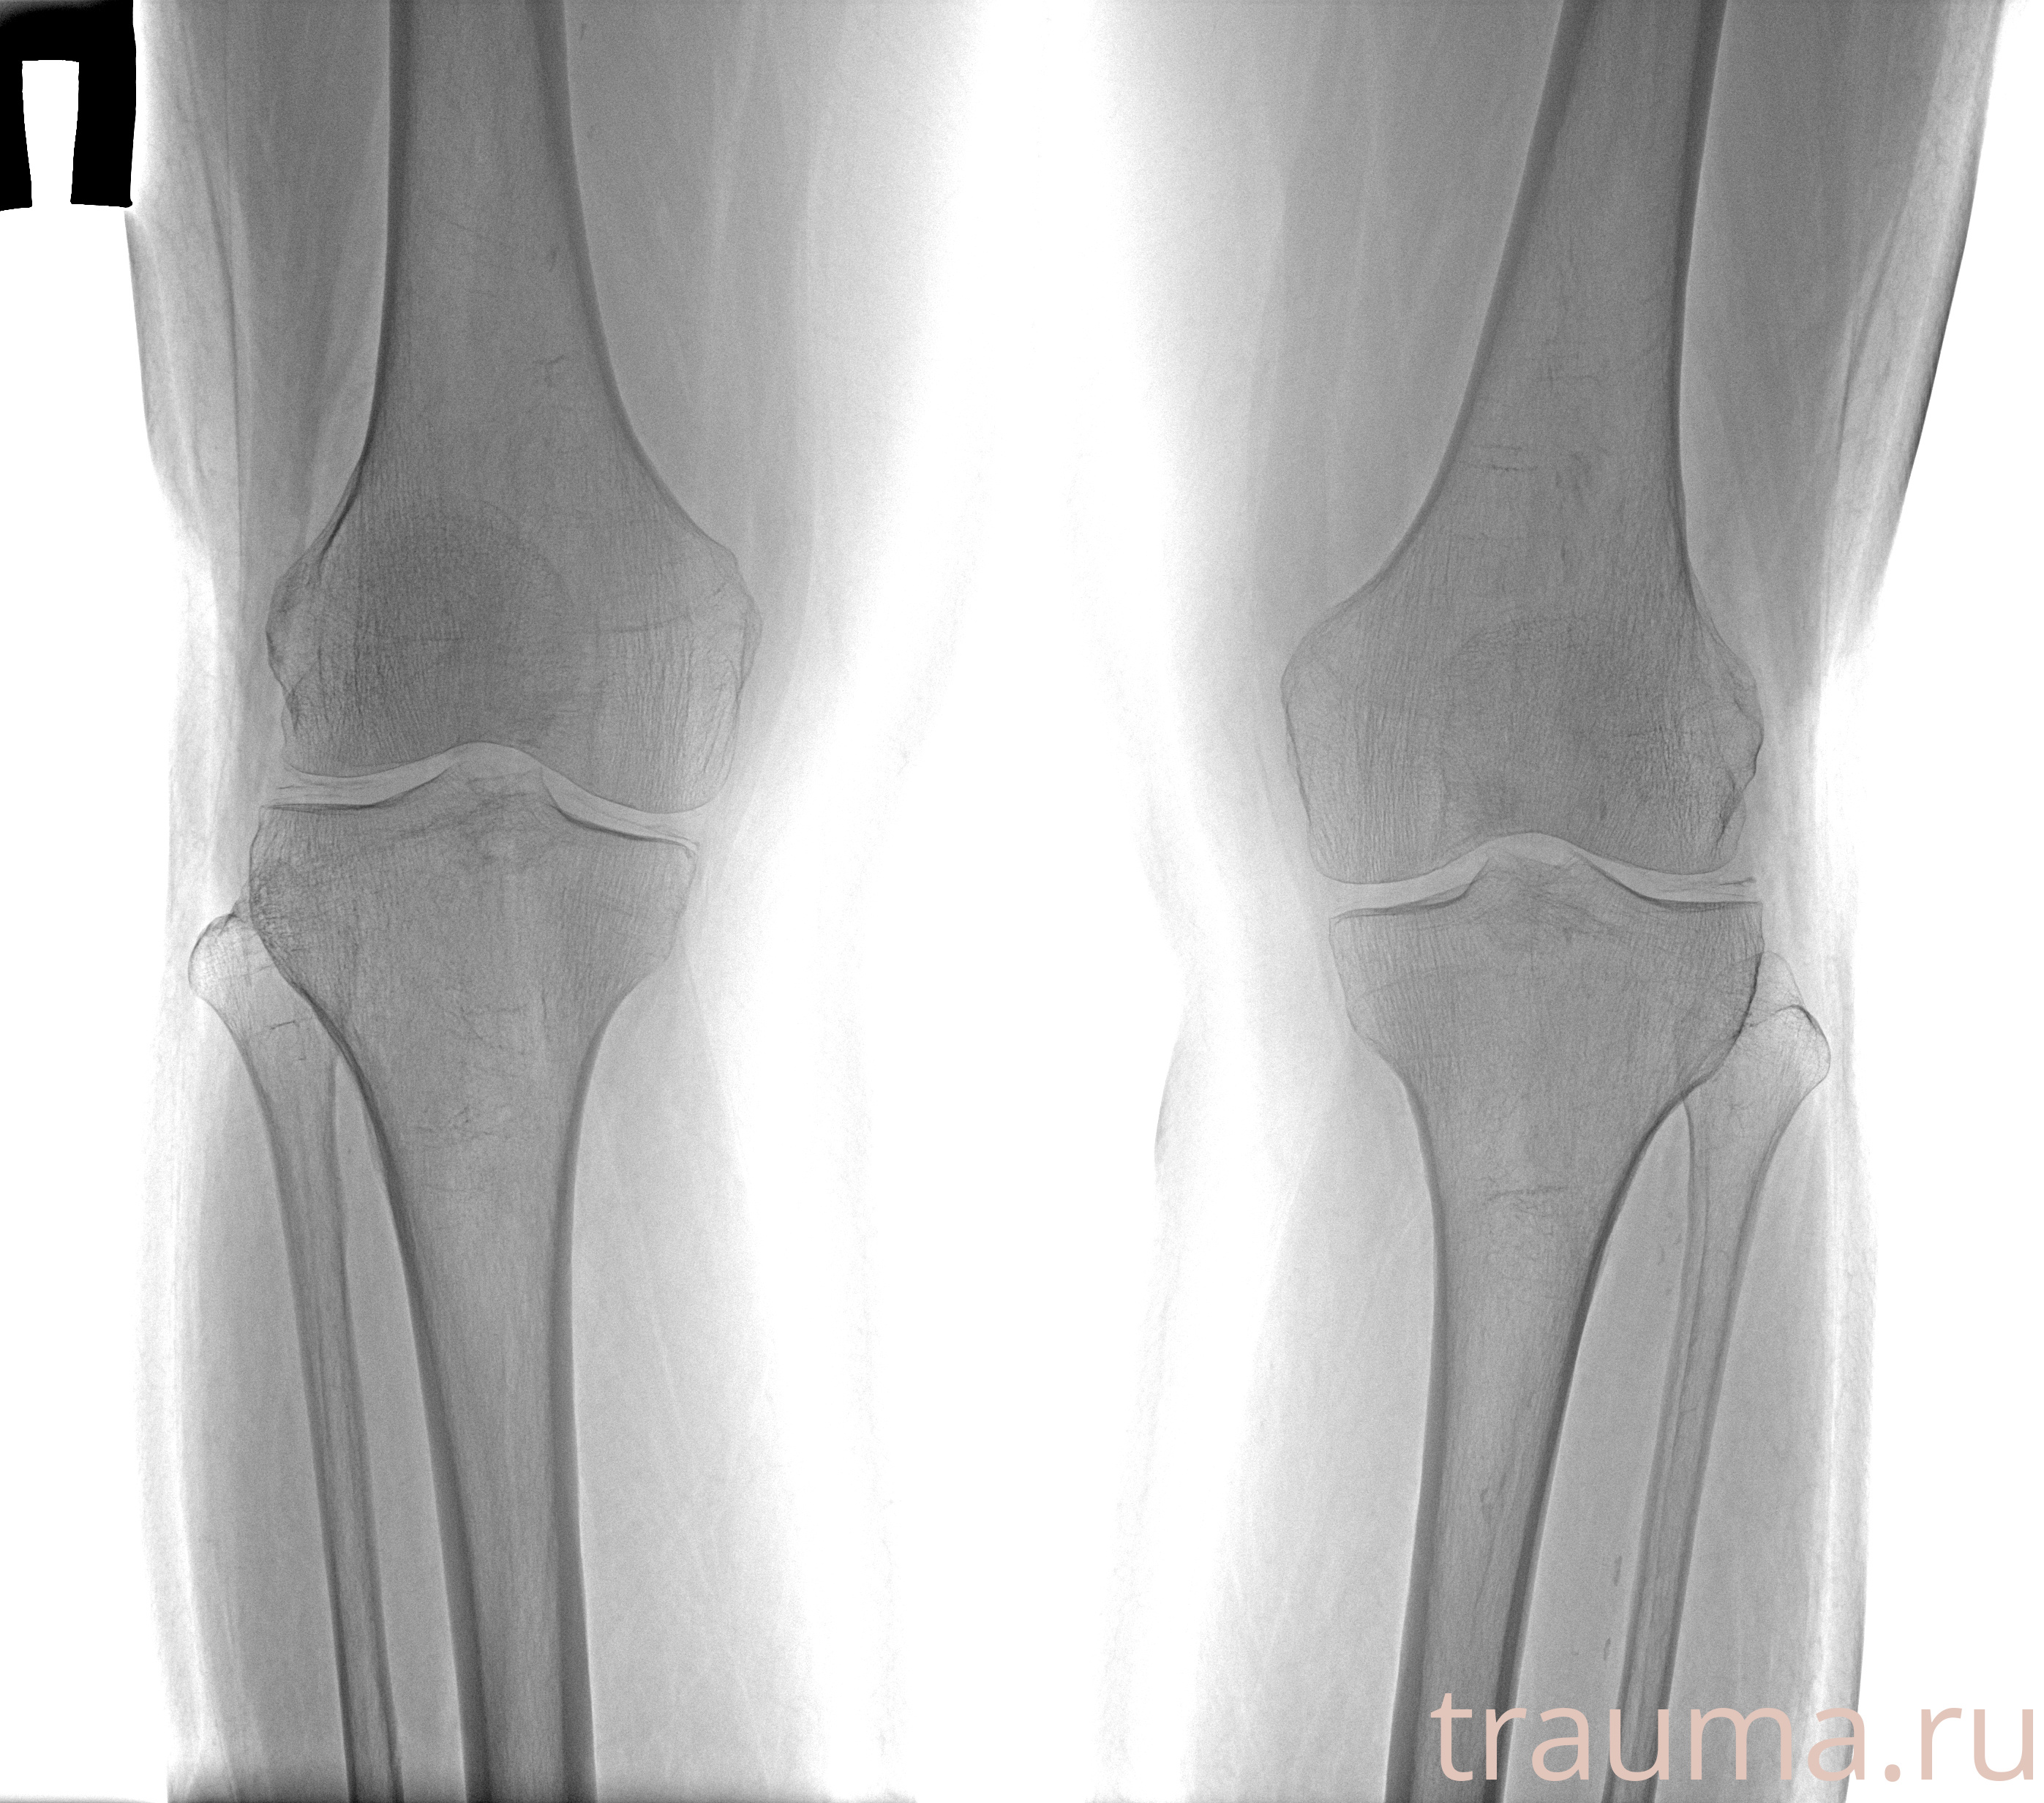

Рентгенограммы

Рентген на дому: по вашему адресу приезжает врач-рентгенолог, травматолог-ортопед с мобильным рентгеновским аппаратом, проводит диагностику травмы или заболевания, делает необходимые рентгенограммы, дает рекомендации по дальнейшему лечению. Получить качественные снимки в домашних условиях возможно благодаря уникальной методике, разработанной МосРентген Центром для института  Склифосовского